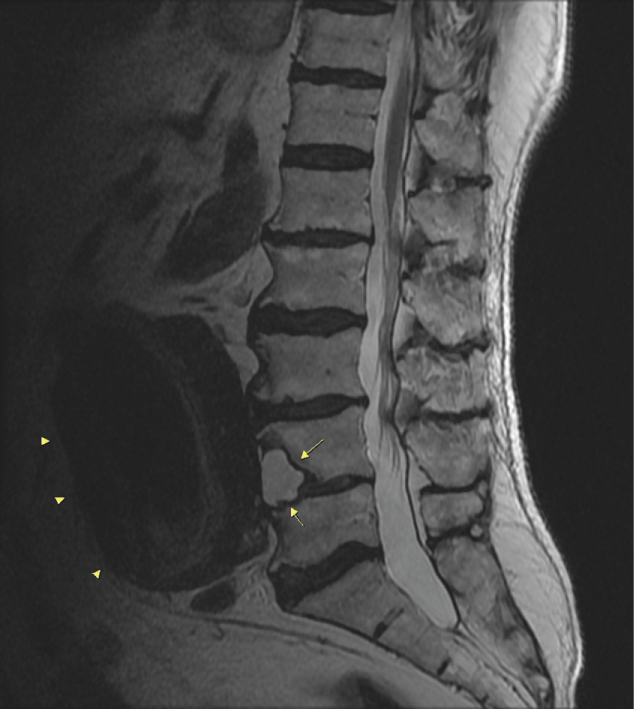

Case 1: A 71-year-old man with low back pain for more than a year, cortical erosion and vertebral cyst formation of L4 vertebral body were diagnosed on lumbar MRI. There was no compression fracture or bone marrow edema. The fusiform unruptured aneurysmatic dilatation of abdominal aorta was seen adjacent to the vertebral cyst (Figure 1 and Figure 2). The vertebral cyst was thought to be associated with abdominal aortic aneurysm (AAA). The aortic wall defect or paraaortic hematoma was not established. After the diagnosis of AAA associated with vertebral cyst, the patient was referred to cardiovascular surgery.

Figure 1: A 71-year-old man, mid-sagittal T2W FSE lumbar MRI image shows sclerotic margin -nonexpansive- hyperintense cyst in L4 vertebral body (long arrows). Giant abdominal aortic aneurysm is also seen adjacent to the anterior margin of L4 vertebra (arrow head). View Figure 1